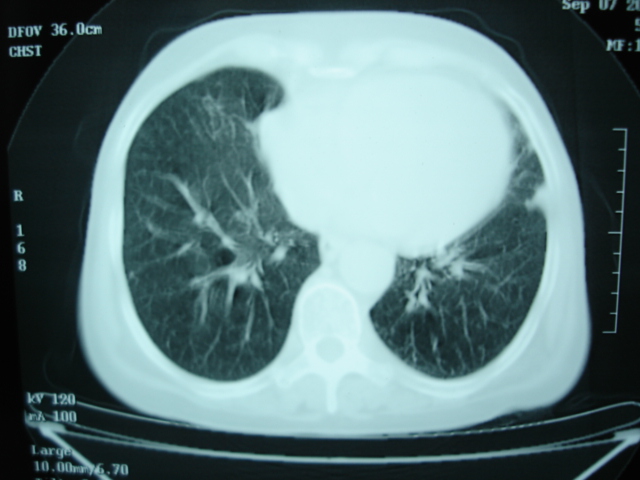

以下是引用卜一在2009-9-7 19:51:00的发言:[br][br] 1 左侧胸内甲状腺占位-多考虑甲状腺腺瘤! 2、左肺门占位-建议增强扫描以便明确性质。 3 慢支并感染! [br]

以下是引用shibing在2009-9-7 20:40:00的发言:[br]左侧胸内甲状腺占位-多考虑甲状腺腺瘤! 2、左肺门占位-建议增强扫描以便明确性质。 3 慢支并感染! [br]